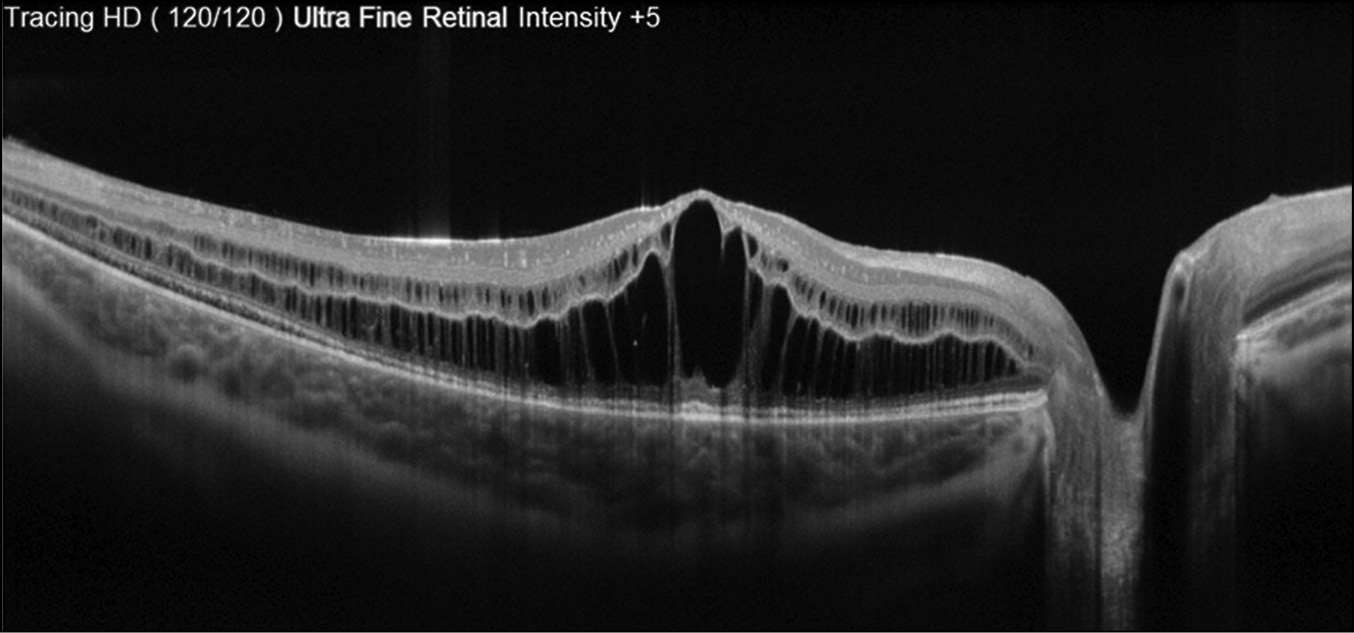

По данным ОКТ, выявлен кистовидный макулярный отёк и отсутствие слоя фоторецепторов в периферических отделах нейроэпителия (рис. 4).

Рис. 4. Кистовидный макулярный отёк и отсутствие слоя фоторецепторов в периферических отделах.

Fig. 4. Cystic macular edema and the absence of a layer of photoreceptors in the peripheral regions.